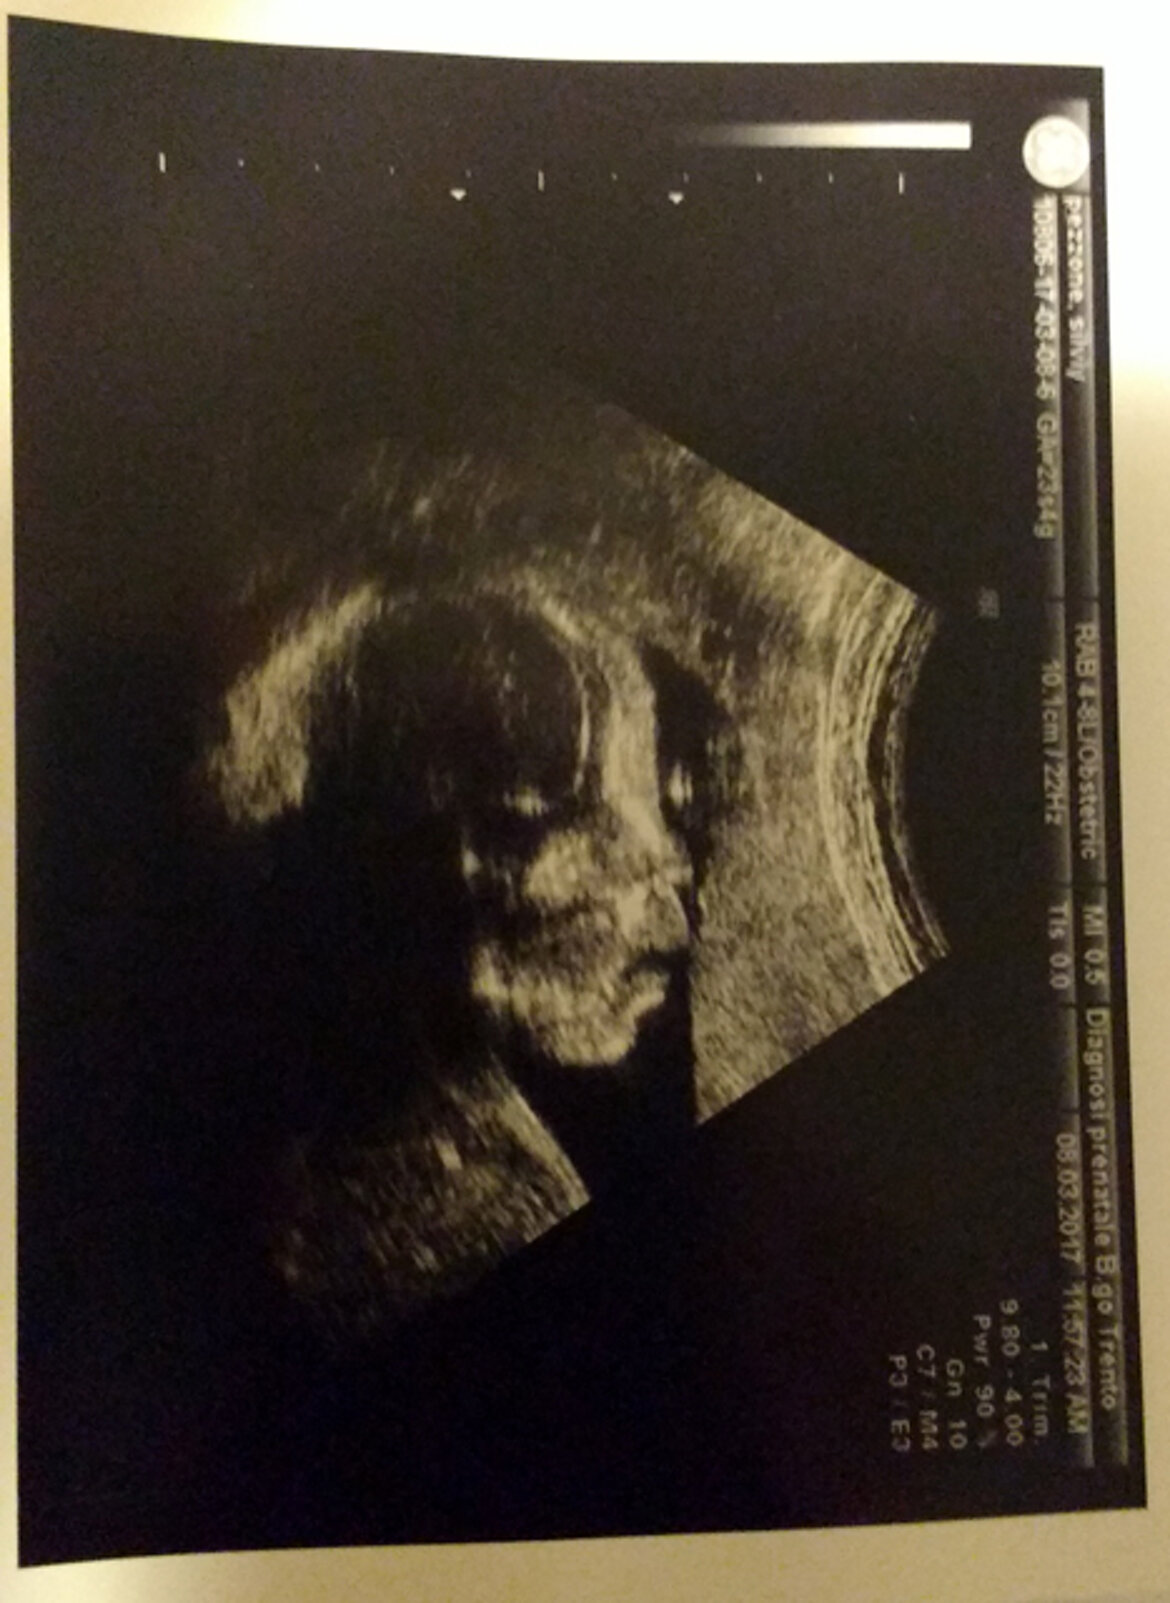

Amir era nel pancione della sua mamma quando Aulona era tornata a Verona per il suo 3° intervento cardiochirurgico correttivo nell'arco di 12 mesi. Una ecografia fetale aveva evidenziato problemi ad un rene ... un nuovo pesante stato di ansia per mamma Selvije, già provata per la lunga e delicata storia clinica della primogenita. Da lì la decisione di aspettare che il bimbo venisse alla luce a Verona, in condizioni di sicurezza e adeguata tutela sanitaria.

Aulona e Amir sono arrivati a Verona il 4 marzo, accompagnati da mamma Selvije in dolce attesa, al 4° mese di gravidanza. Il viaggio è stato organizzato non a caso, ma per dar modo ai nostri medici di controllare come cresceva la creatura in arrivo !!! E' stata proprio lei la prima ad essere sottoposta ad una visita specialistica ... una ecografia morfologica e un ecocardio fetale, per sapere che tutto stava procedendo bene! Non ci è stato svelato se sarà "una lei o un lui", mamma Selvije non ha voluto saperlo.